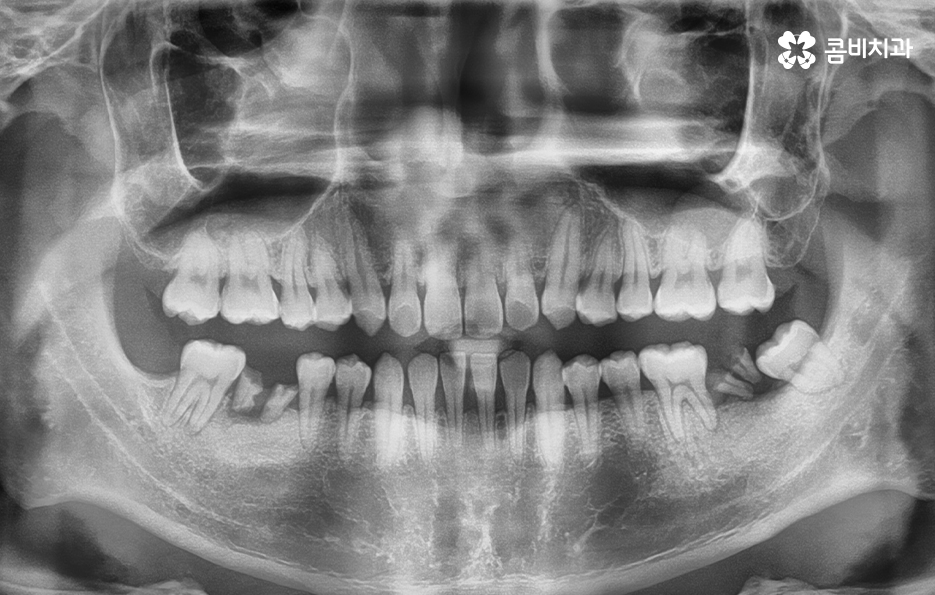

위 환자분의 경우 충치로 인해 오른쪽 아래 제1대구치와

왼쪽아래 제2대구치가 상실된 상태였으며, 치아교정만으로는

치료가 불가능한 케이스였기 때문에 비발치 교정으로

진행하면서 외과수술이 병행된 케이스라고 할 수 있어요

클리피씨교정을 통해서 약 1년 6개월간

치료가 진행이 되었고, 수술과 병행이되며, 치료 마무리 단계에서

임플란트 수술까지 진행이 된 사례라고 볼 수 있는데요.